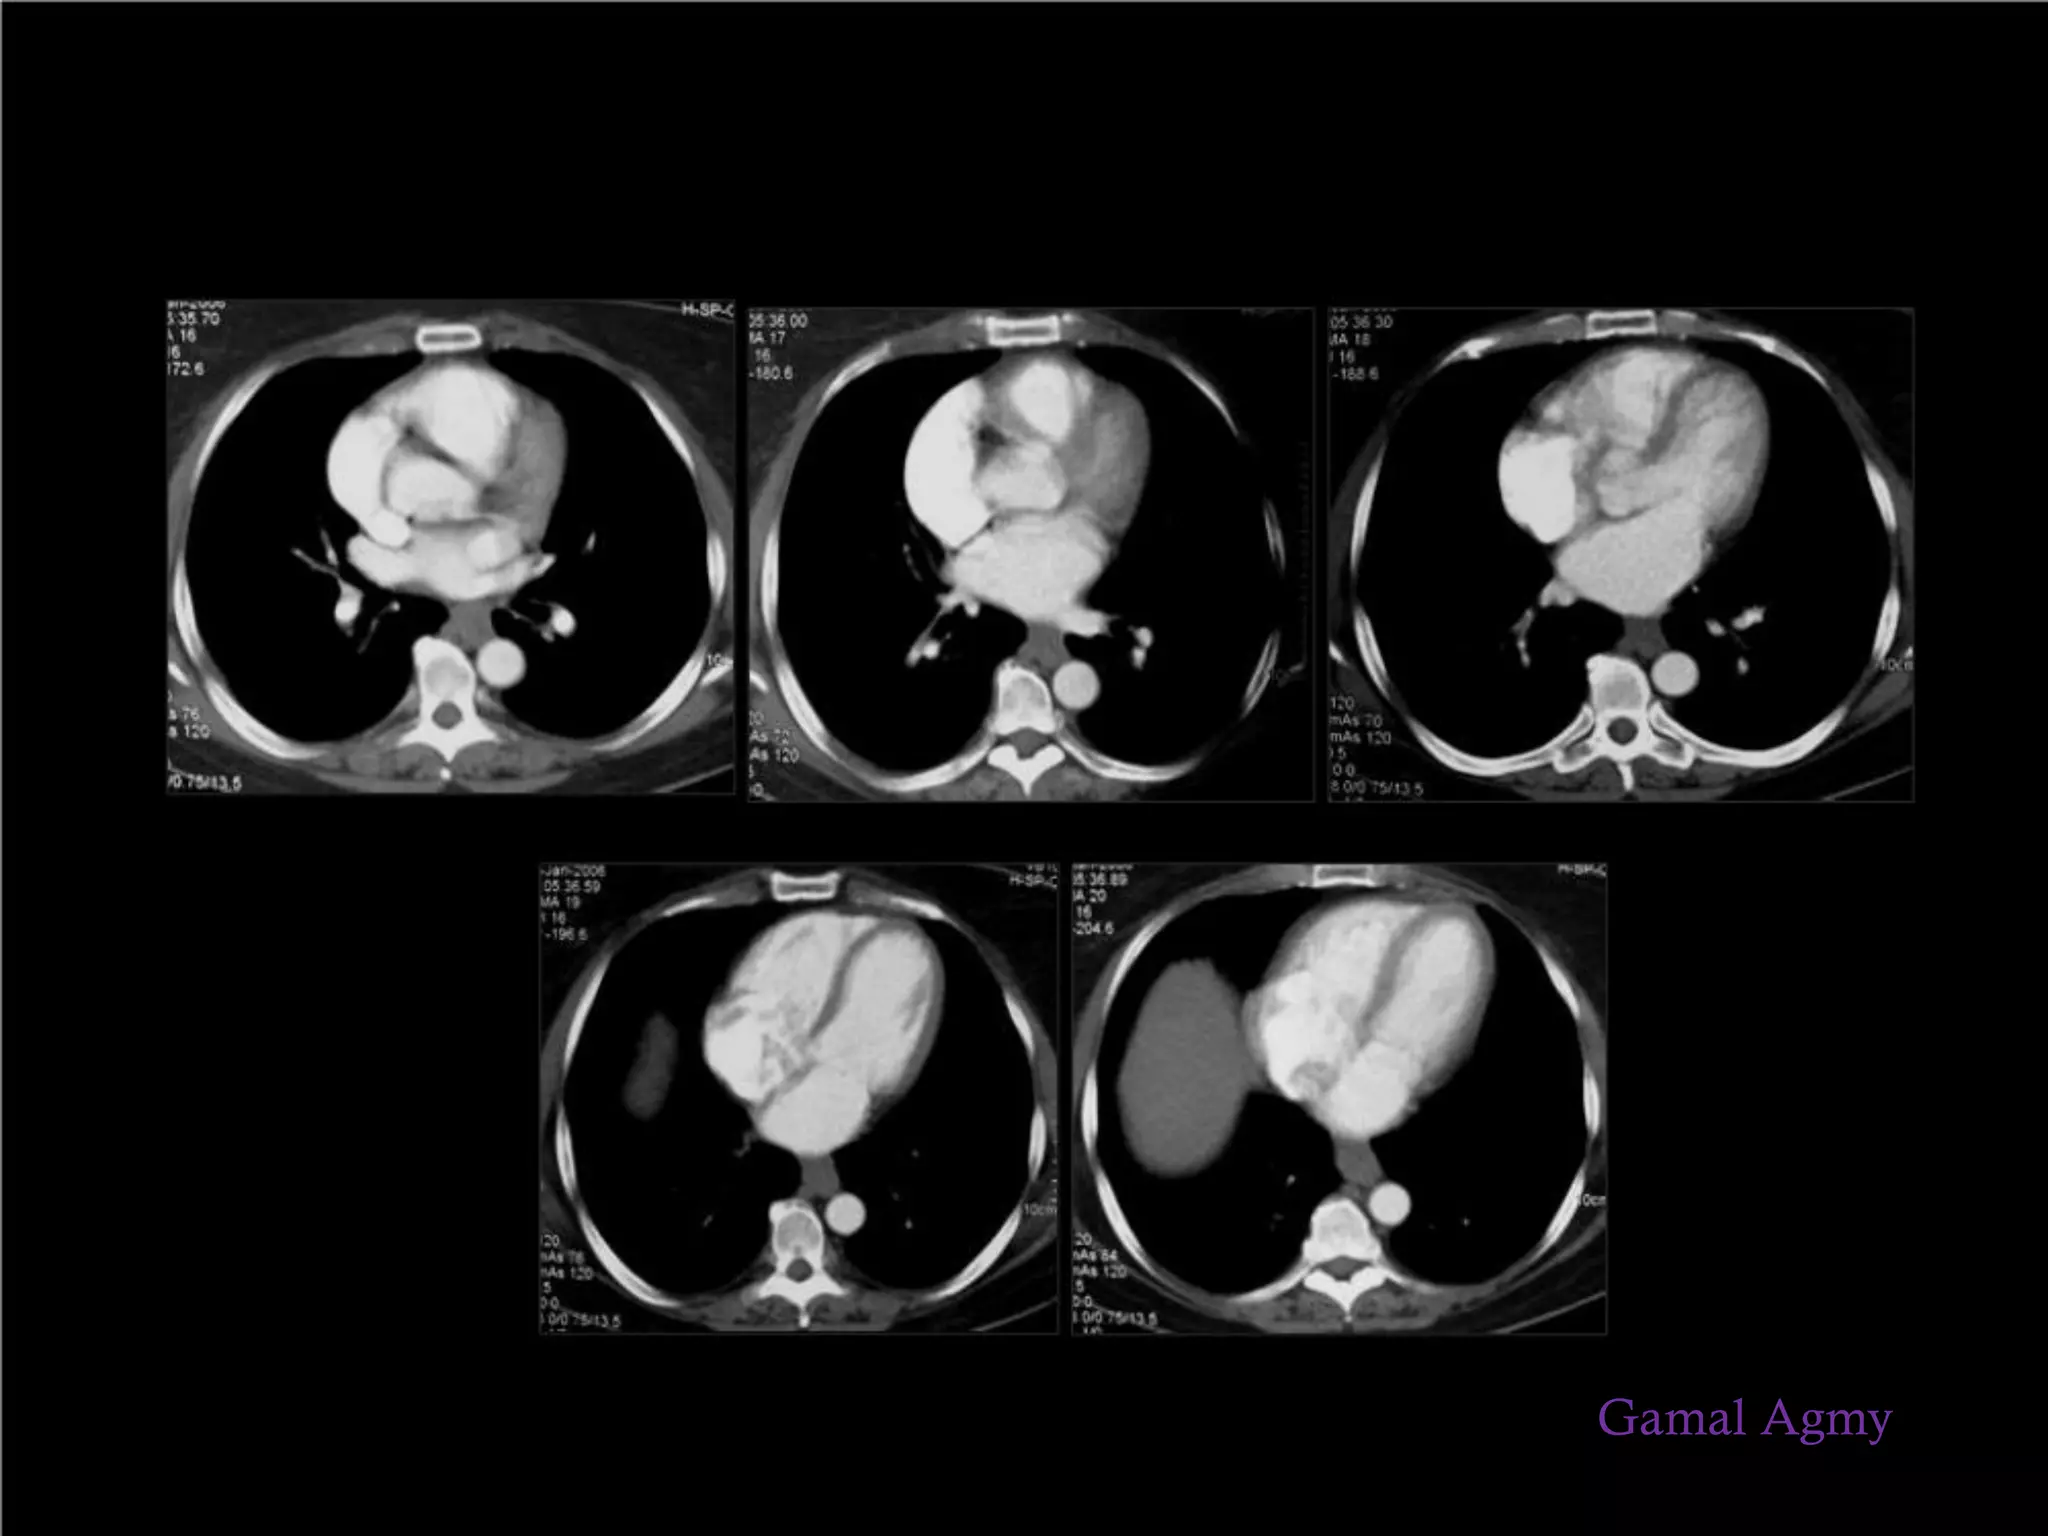

Vascular abnormalities

Gamal Agmy

③ Differential diagnosis of

mediastinal disease - Middle